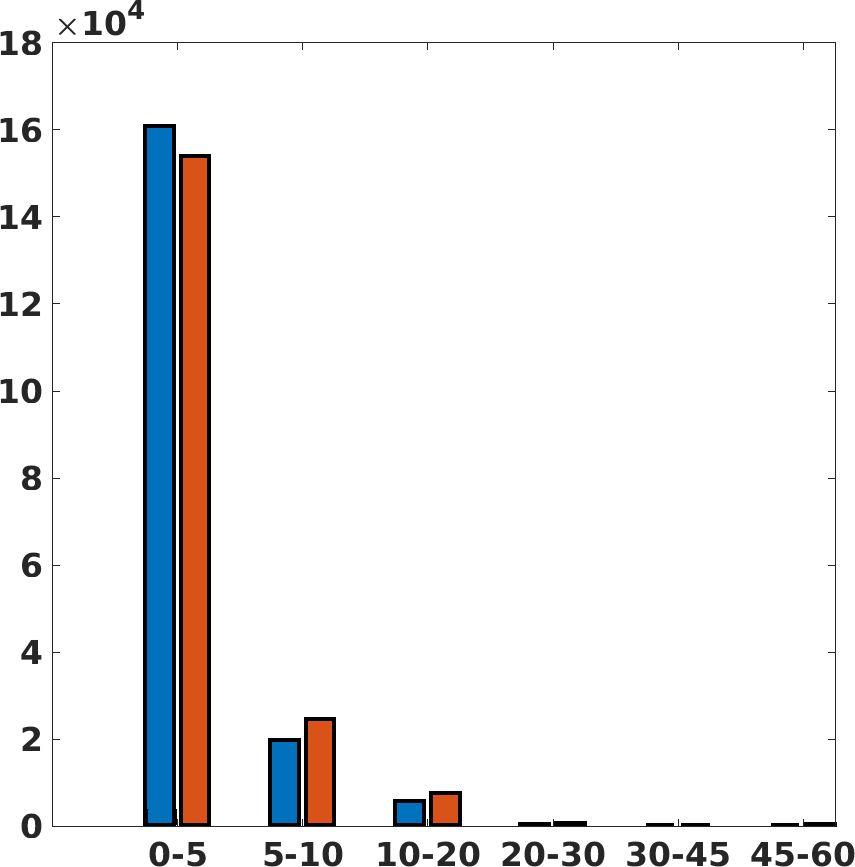

Fig. 7(a-b-c, right) shows the histogram of the absolute value of the error with respect to the target image, of the prediction and Cubic convolution results, respectively. The histograms show the number of pixels where the prediction error is lower than 5 (i.e., the first bin of the histogram), which means very similar to the target when visually analysing the images. From the Cubic convolution to the predicted images, this value increases of on obstetric 4X raw images, on cardiac 4X raw images, and on abdominal 4X raw images.

Fig. 8 shows the box plot of the SSIM (a-b-c, left) and MAE (a-b-c, right) quantitative metrics, as performed for PSNR metric. Also, these metrics show that our method improves the results of Cubic convolution both in terms of average value and variability. For example, the SSIM median value improves of on obstetric 4X images and the MAE median value improves of on cardiac 2X images.

Fig. 17 (right) shows the histogram of the absolute value of the error with respect to the target, of the prediction and Cubic convolution respectively. This result shows that our framework increase of and (2X and 4X, respectively) the number of pixels where the prediction error is lower than 5, which is very similar to the target when visually analysing the images, and improved with respect to the learning framework applied to raw images. According to Fig. 18, our method improves the accuracy of Cubic convolution. For example, the SSIM increases of on cardiac 2X and the MAE increases of on abdominal 4X.